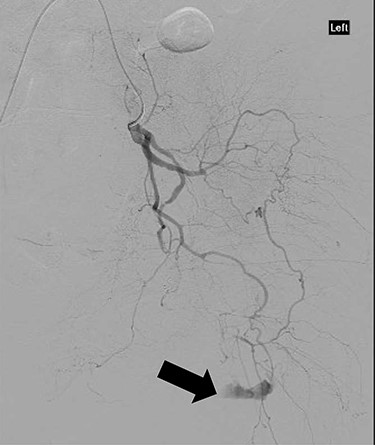

CT angiography showed multiple hypertrophied branches of the left internal iliac artery with heavy collateralisation to the territory of occluded left common femoral artery. Pathological dilatation of the collateral branch of the left obturator artery was identified as source of bleeding and embolized (Fig. 2). A further source of bleeding from a collateral muscular branch of the internal iliac artery was also embolized (Fig. 3).

CT angiography with dye showing dilatation of collateral branch of left obturator artery.